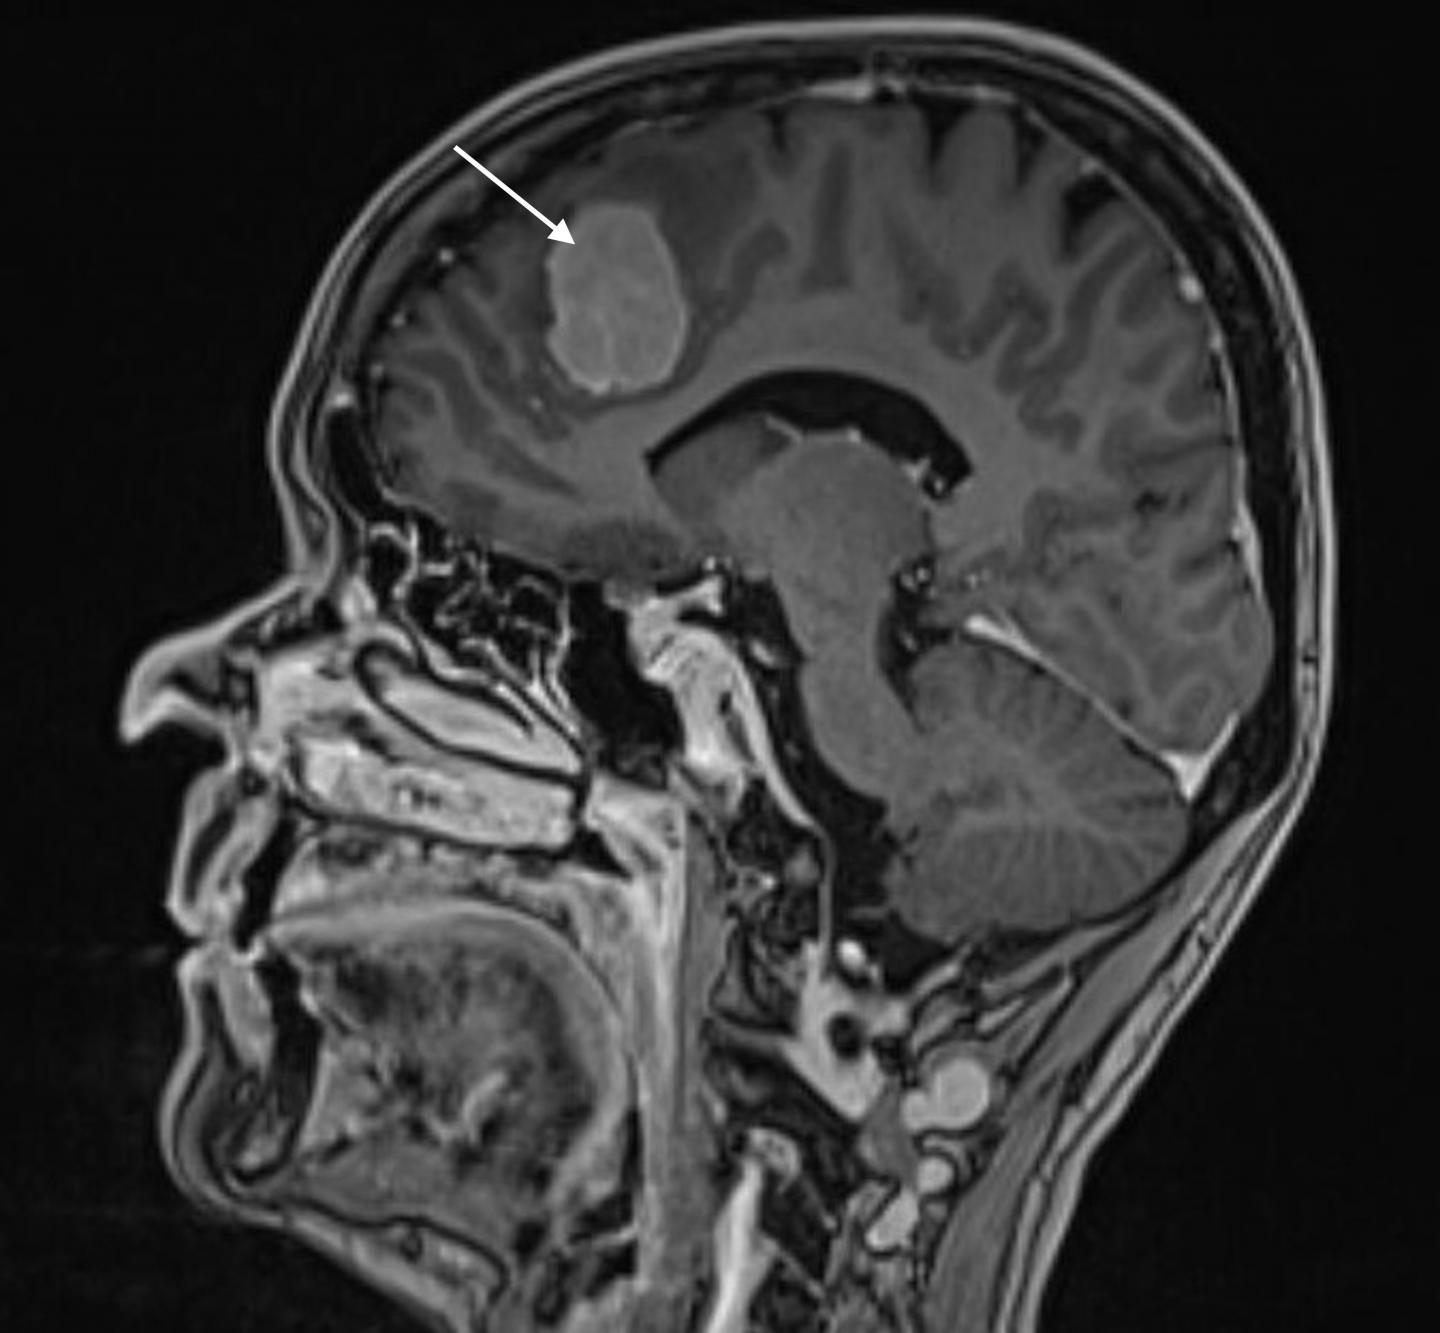

image: Magnetic image of meningioma.

Meningiomas, which originate in the meninges surrounding the brain, are the most common type of benign brain tumours. The primary treatment for meningiomas is neurosurgery. Since the risks associated with surgical treatment increase as people get older and develop other diseases, over 80-year-old patients with brain tumours are not operated on almost anywhere in the world.